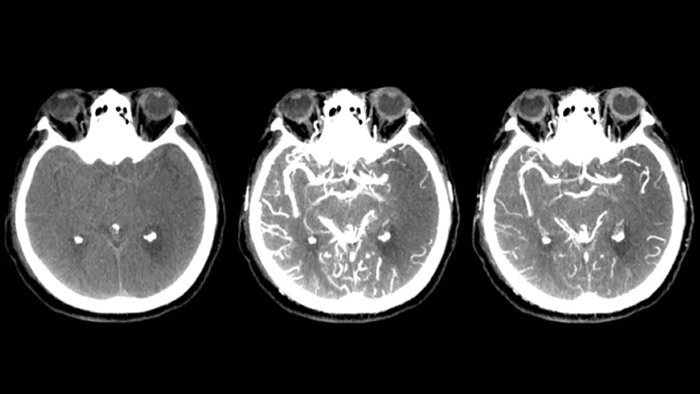

SmartCT Soft Tissueは、軟部組織をCTのように可視化し、3つの方法で脳卒中診断を支援します。非造影スキャンは、早期虚血性変化の検出に役立ちます。造影スキャンの早期フェーズでは、近位閉塞の識別に役立ちます。造影スキャンの後期フェーズでは、側副路の検出をサポートします。

Dual Viewにより造影コーンビームCT撮影の早期相画像と後期相画像を並べて表示するデュアルビュー機能により、ペナンブラの識別や側副血行路の確認が可能です。